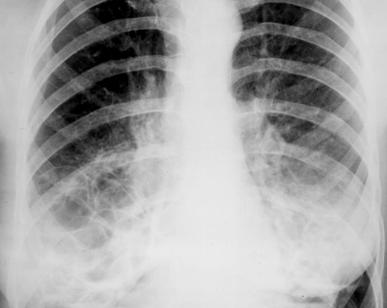

Fig. 11 – Bronsiectazii bazale bilaterale